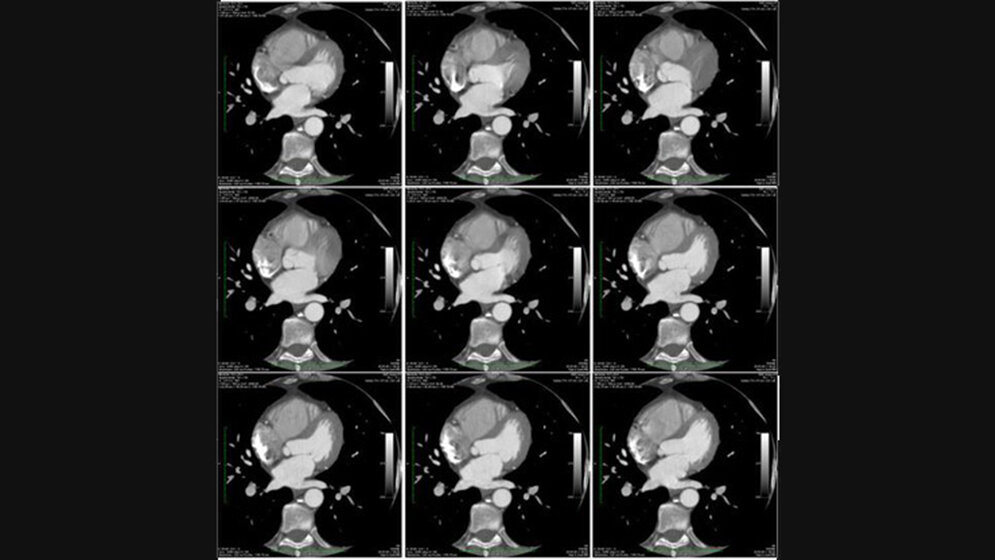

Nach der Patienten- und Untersuchungsvorbereitung folgt nun die strukturierte Untersuchungsdurchführung. Auch hier empfi ehlt sich die strukturierte Vorgehensweise. Lernen Sie wie Sie Kardio-CT Untersuchungen (Calcium Score und Kardio-CTA) planen und welche Scantechnik sich für die unterschiedlichen Patienten besonders gut eignet. Darüber hinaus fi nden Sie Tipps, die Ihnen die Arbeit bei der Wahl der besten Rekonstruktionsphase erleichtern.